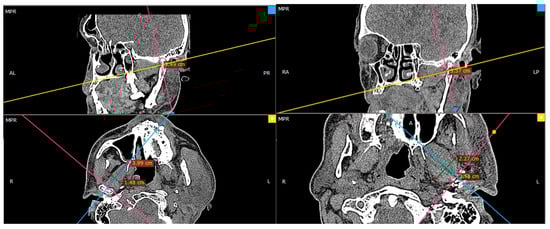

There is no doubt that surgical correction is the only way to restore the anatomical position of the mandibular head; however, the question is if it also improves the condition of the lateral pterygoid muscle, which, at first glance, right after the injury, shows significant asymmetry in terms of its shape (Figure 2).

Figure 2. Radiologic imaging study result in a patient with a fracture of the right mandibular head. Shortening of the right lateral pterygoid muscle (red arrow). Please note the length of the muscle on the intact side (blue arrow).